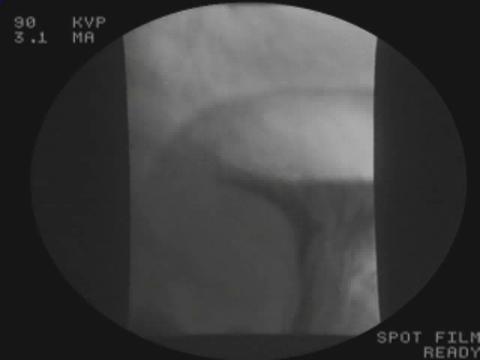

Barium Swallow: Fluoroscopy

Fluoroscopy (a continuous x-ray technique) is used to view the esophagus after a person swallows liquid barium.

In this video, the esophagus can be seen contracting as barium passes through it into the stomach and small intestine.